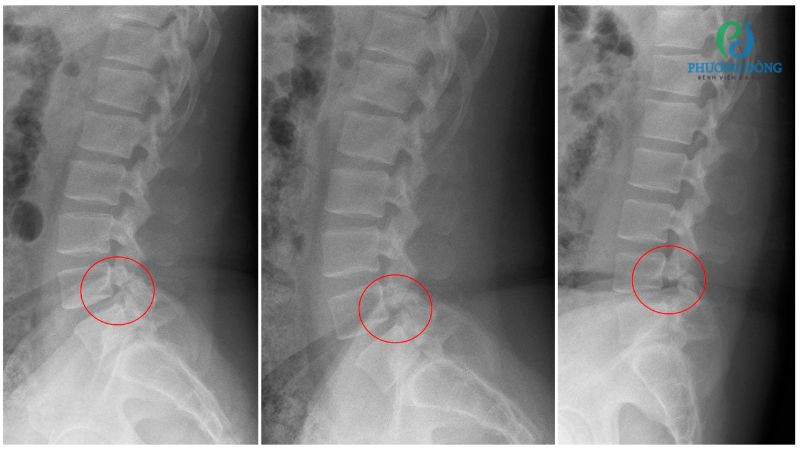

- Thoát vị đĩa đệm, thoái hóa cột sống nghiêm trọng.

- Rạn thân đốt sống do loãng xương.

- Tai nạn dẫn tới chấn thương cột sống.